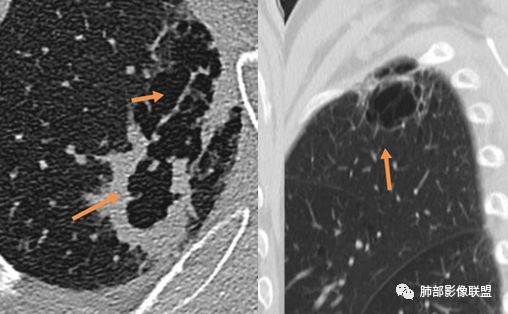

1.左肺上叶应为空腔样病灶。如作为空洞,前下壁并不完整,且与薄壁囊腔壁相延续,整体结合起来看应为厚薄不均匀的较大的空腔样病灶。这样的空腔样病灶应首先怀疑空腔性肺癌。

空腔性肺癌主要见于腺癌和鳞癌,上述2-5项更倾向鳞癌。

6.胸膜受侵,胸膜外脂肪密度增高;外缘膨隆为主。

病理上在肺纤维化蜂窝区和相邻肺气肿交界区域常常会观察到肺泡上皮反复增生及支气管上皮鳞状细胞化生,然后通过不典型增生最后导致细胞恶性转化。并且有人认为且肺纤维化瘢痕可以导致淋巴管阻塞,局部潜在致癌物质增多,使得在该背景下容易发生肺癌。所以即使病灶形状不一定呈肿瘤样膨胀生长,但位于局限的肺气肿与肺纤维化交界区也需谨慎观察。